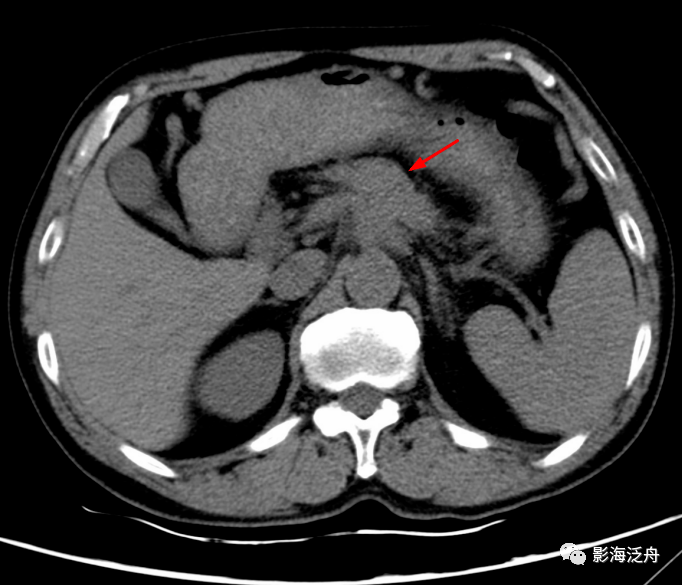

胸部CT平扫纵膈窗的最后两个层面显示腹主动脉前方不规则软组织肿块(红箭) , 轮廓模糊不清 , 似乎包绕整个腹腔干 , 结合患者腹痛症状 , 大概率是胰腺癌 。 但这个病人在胸部CT检查报告中并未提及此处病变 。 不过好在患者第二天又做了全腹部增强CT检查 , 如下↓